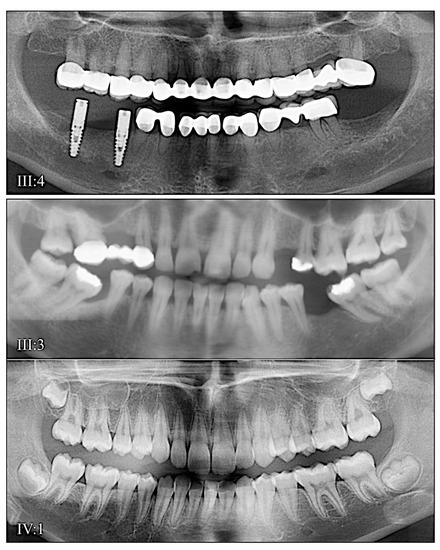

3.3. Eight Families with 3′ DSPP Mutations Causing DD-II or DGI-II

| 7 | Illumina HiSeq 2500 (WES) | NG_011595.1:g.11268delA; NM_014208.3:c.2134delA; NP_055023.2: p.(Ser712Alafs*602) | −1 Frameshift | III:1, affected 1st child: 203.26× |

| 8 | PacBio SMRT | NG_011595.1:g.11659delG; NM_014208.3:c.2525delG; NP_055023.2:p.(Ser842Thrfs*472) | −1 Frameshift | |

| 9 | PacBio SMRT | NG_011595.1:g.11659delG; NM_014208.3:c.2525delG; NP_055023.2:p.(Ser842Thrfs*472) | −1 Frameshift | |

| 10 | PacBio SMRT | NG_011595.1:g.12269delC; NM_014208.3:c.3135delC; NP_055023.2:p.(Ser1045Argfs*269) | −1 Frameshift | |